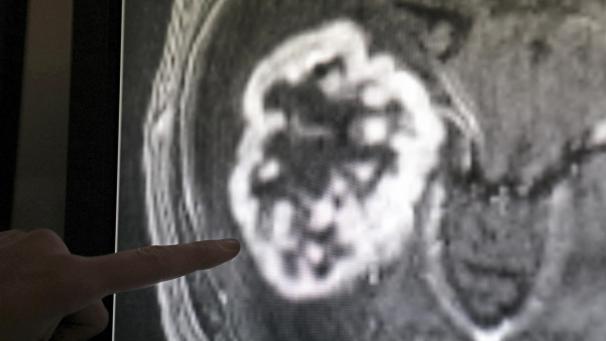

Laut Weltgesundheitsorganisation (WHO) wird die Zahl der Krebserkrankungen in den nächsten Jahrzehnten stark ansteigen. Die Folgen werden jedoch von Land zu Land sehr unterschiedlich sein. Je höher der Entwicklungsstand, desto geringer ist das Sterberisiko. Die Stiftung gegen Krebs sieht hierzulande positive Entwicklungen, es bleibe aber noch viel zu tun.